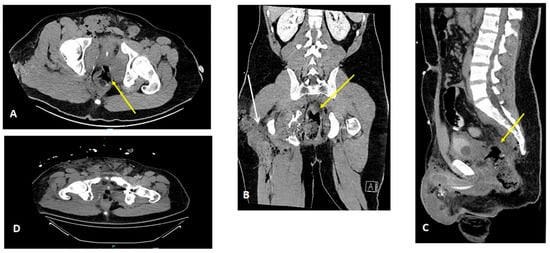

A 22-year-old male was evacuated from the war zone after sustaining multiple wounds from a pelvic blast caused by an anti-tank-guided missile. Following initial resuscitation at the Hadassah Hebrew University Medical Center in Jerusalem, including the administration of two units of whole blood, a pelvic injury assessment revealed significant wounds, including active bleeding in the right lateral–posterior thigh and a suspected exit wound in the left groin. The patient had intact lower extremity strength, sensation, and peripheral pulses. There was no blood at the urethral meatus, and a rectal examination revealed fresh blood with a preserved sphincter tone. Initially, packing was performed in the thigh wound and rectum. Contrast-enhanced CT imaging revealed an entry wound in the right thigh, a crushed ischium, a rectal injury with free air in adjusted perirectal tissue, and an S4 vertebra fracture (Figure 1). No vascular or bladder injuries were identified. During urgent surgery, the patient was positioned in lithotomy. An examination under anesthesia revealed rectal bleeding and 240-degree circumferential lacerations in the anterior wall 10 cm from the anal verge; hemostasis was achieved with cautery and packing. A loop sigmoid colostomy was performed without distal washout or pre-sacral drainage. Laparoscopic exploration showed minor fluid but no enteric contamination.

Figure 1. Initial CT scan findings following resuscitation. A contrast-enhanced CT scan of the abdomen and pelvis showing axial, coronal, and sagittal sections (AD). Perforation in the lateral–anterior rectal wall, following initial packing ((AC), yellow arrow). Packing was also conducted for the right thigh wound ((B), white arrow). Complex pelvic fracture with embedded foreign metal bodies is also shown (D).